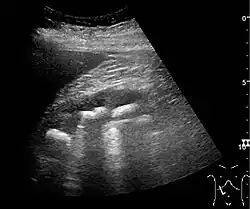

The kidney is divided into parenchyma and renal sinus. The renal sinus is hyperechoic and is composed of calyces, the renal pelvis, fat and the major intrarenal vessels. In the normal kidney, the urinary collecting system in the renal sinus is not visible, but it creates a heteroechoic appearance with the interposed fat and vessels. The parenchyma is more hypoechoic and homogenous and is divided into the outermost cortex and the innermost and slightly less echogenic medullary pyramids. Between the pyramids are the cortical infoldings, called columns of Bertin (Figure 1). In the pediatric patient, it is easier to differentiate the hypoechoic medullar pyramids from the more echogenic peripheral zone of the cortex in the parenchyma rim, as well as the columns of Bertin (Figure 2).[1]

Figure 2. Normal pediatric kidney. * Column of Bertin; ** pyramid; *** cortex; **** sinus.[1]